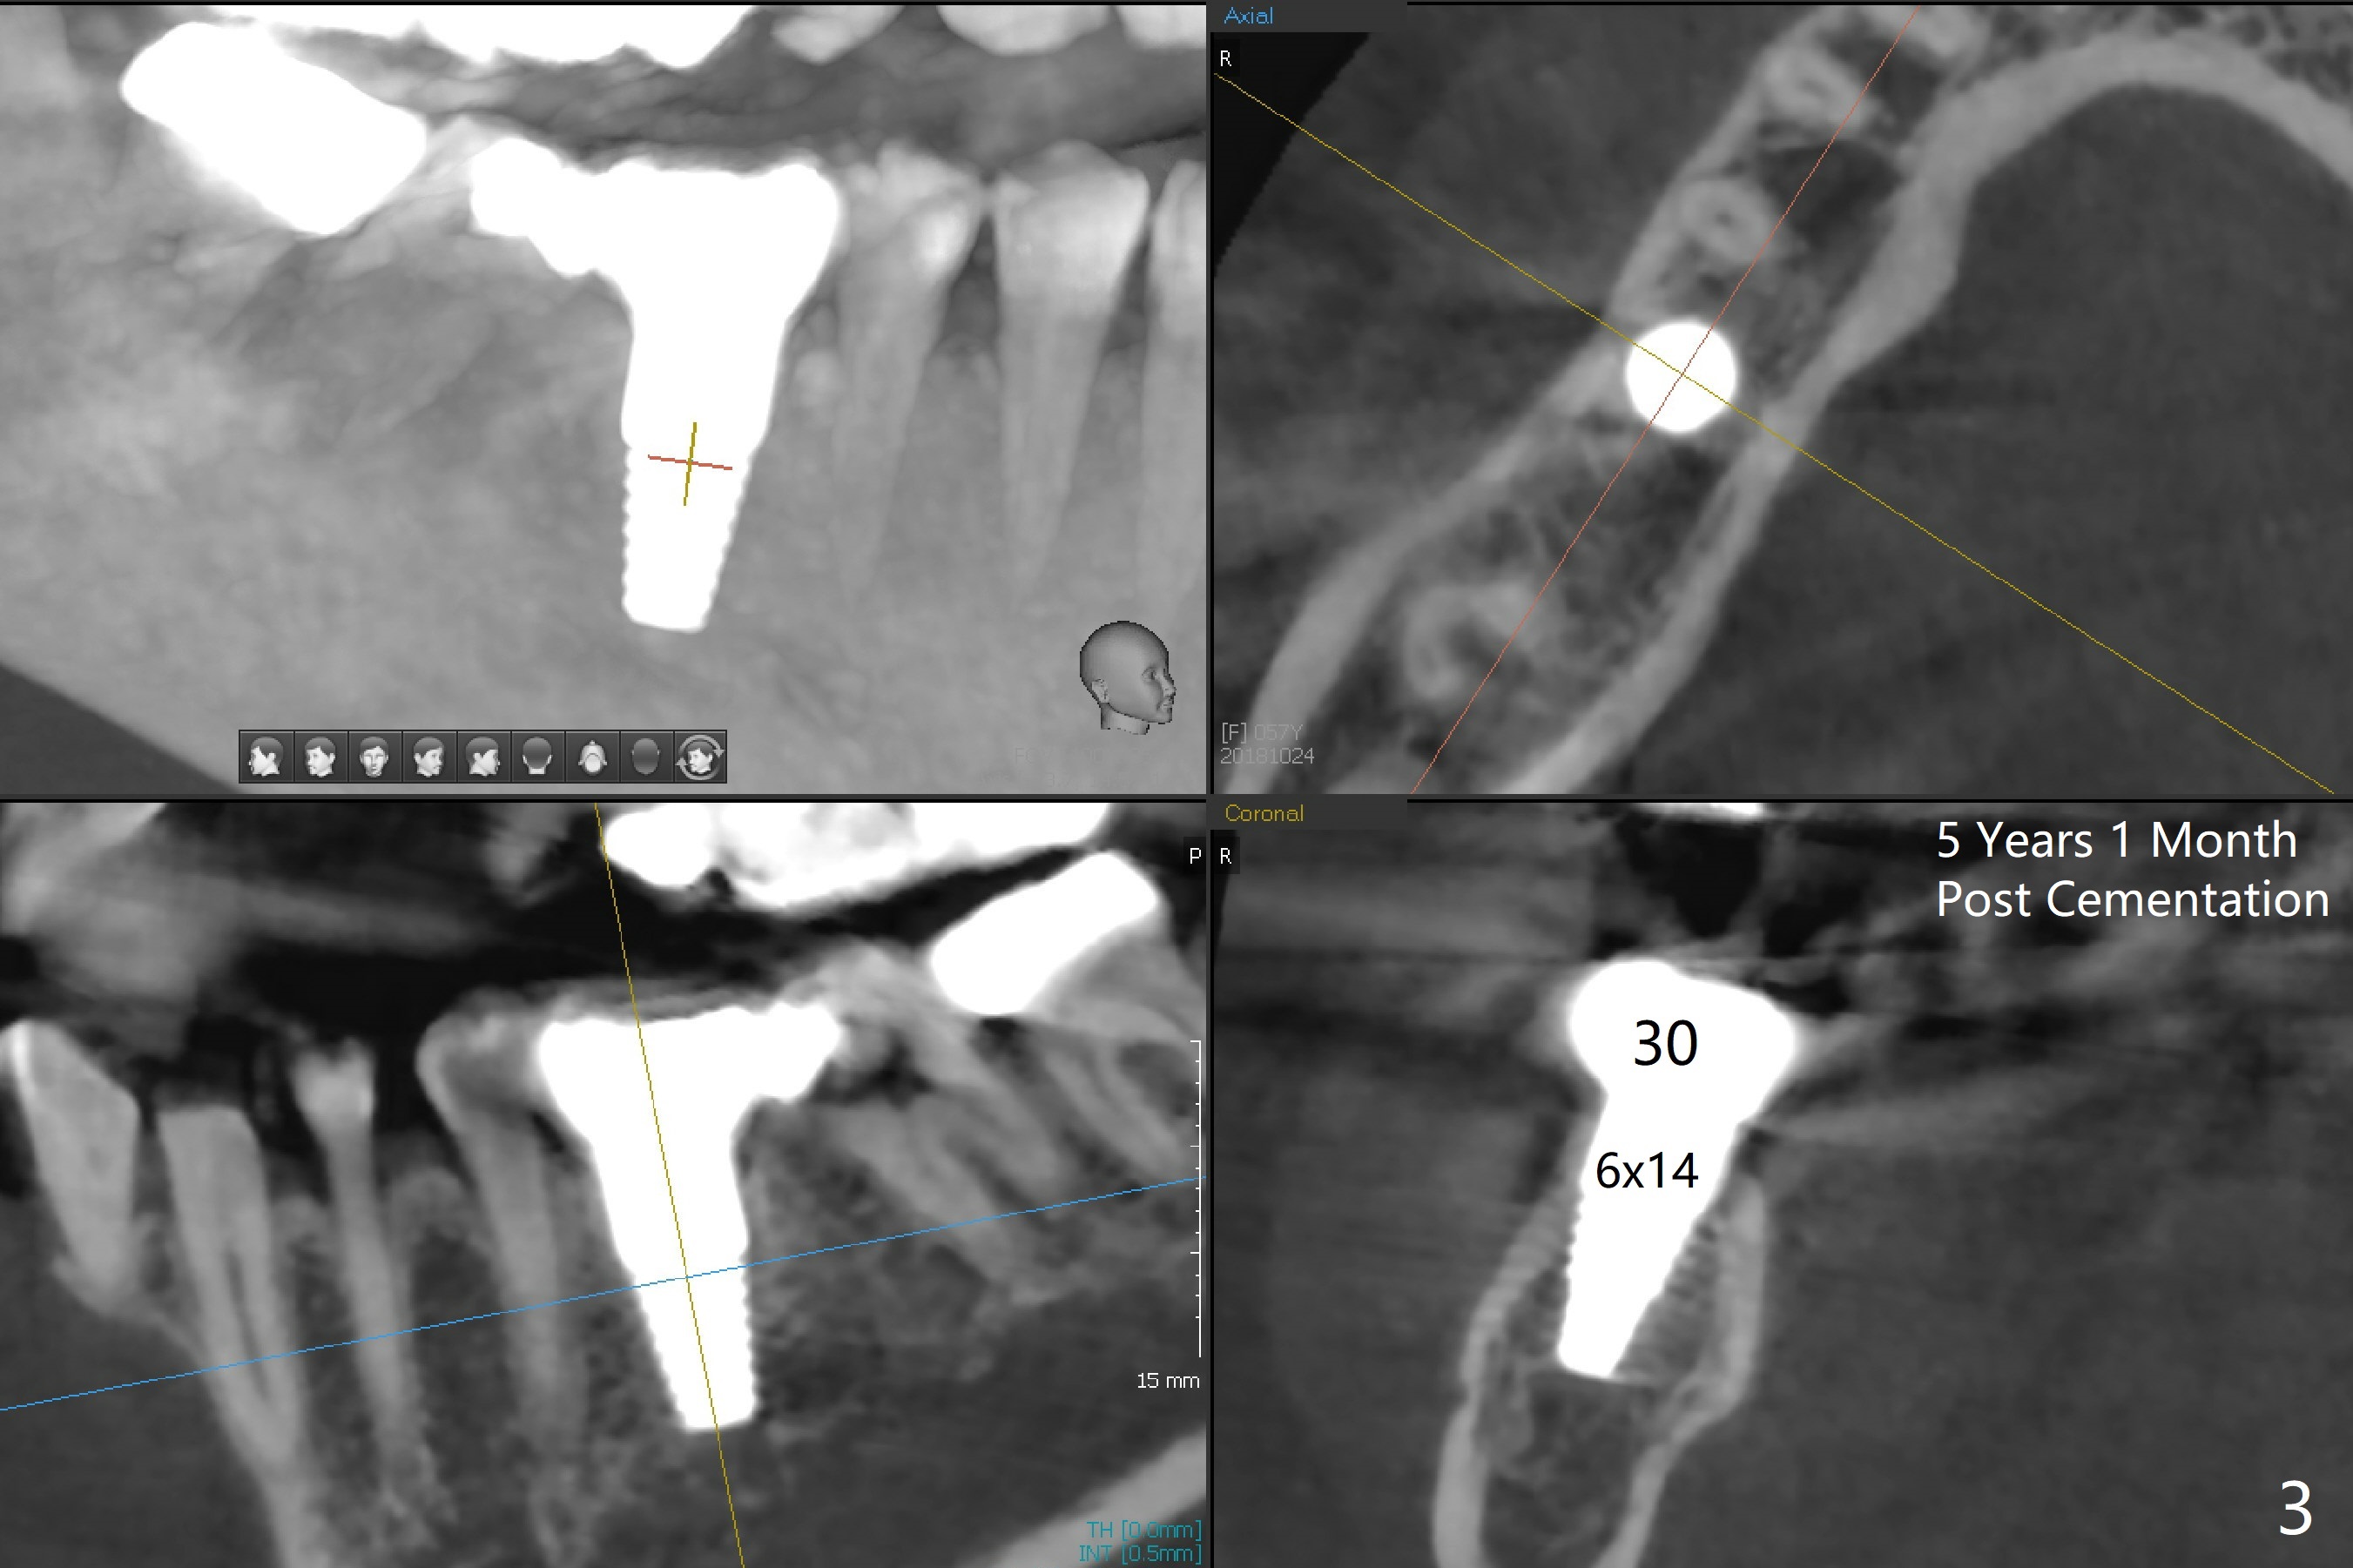

A 57-year-old woman returns with pain in the upper right quadrant (Fig.1,2). In fact the mesiobuccal root of the tooth #2 has vertical fracture. Although the socket destruction at #3 is not as extensive as that of #2, the socket of #3 has communication with the sinus. Prior to socket preservation, a piece of Osteogen plug is inserted at #3. PRF should be prepared for severe bone loss. In contrast there is no bone loss around the implants at #19 or #30 (Fig.1,3,4). Although the socket at #2 is slightly open 9 days postop, bone graft appears to be present (Fig.5). The bone at #2 and 3 seems to regenerate 7 months post socket preservation (Fig.6). Three short implants seem to be better than 2 implants for 3-unit FPD (Fig.7-9).